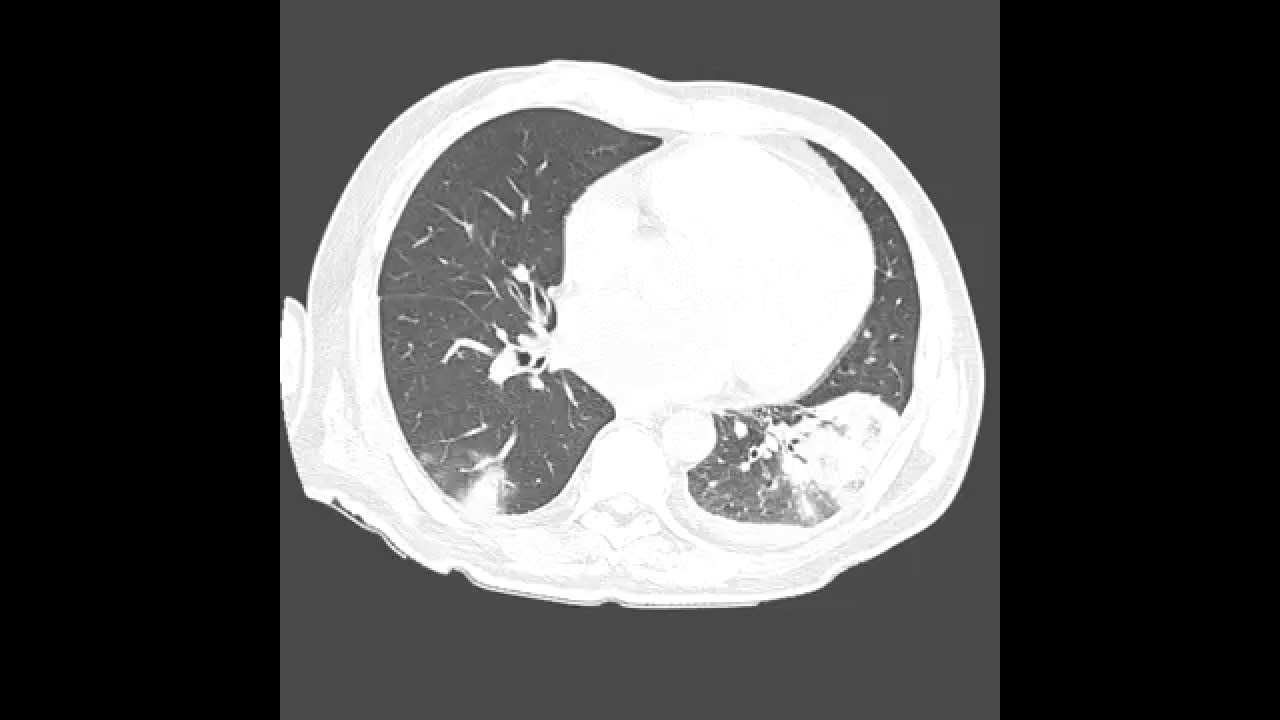

Участки по типу консолидации